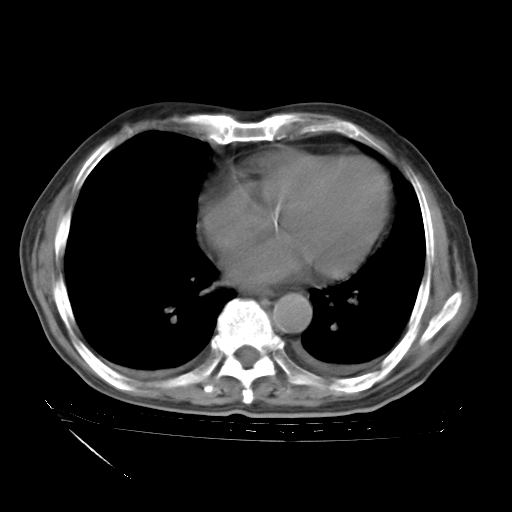

甲强龙80mg/日+抗结核治疗(异烟肼+利福霉素+乙胺丁醇)10天。复查肺部CT。

治疗10天肺部CT

94186 3 10.bmp

94186 3 11.bmp

94186 3 12.bmp

94186 3 13.bmp

94186 3 14.bmp

94186 3 15.bmp

94186 3 16.bmp

94186 3 17.bmp

94186 3 18.bmp

94186 3 19.bmp